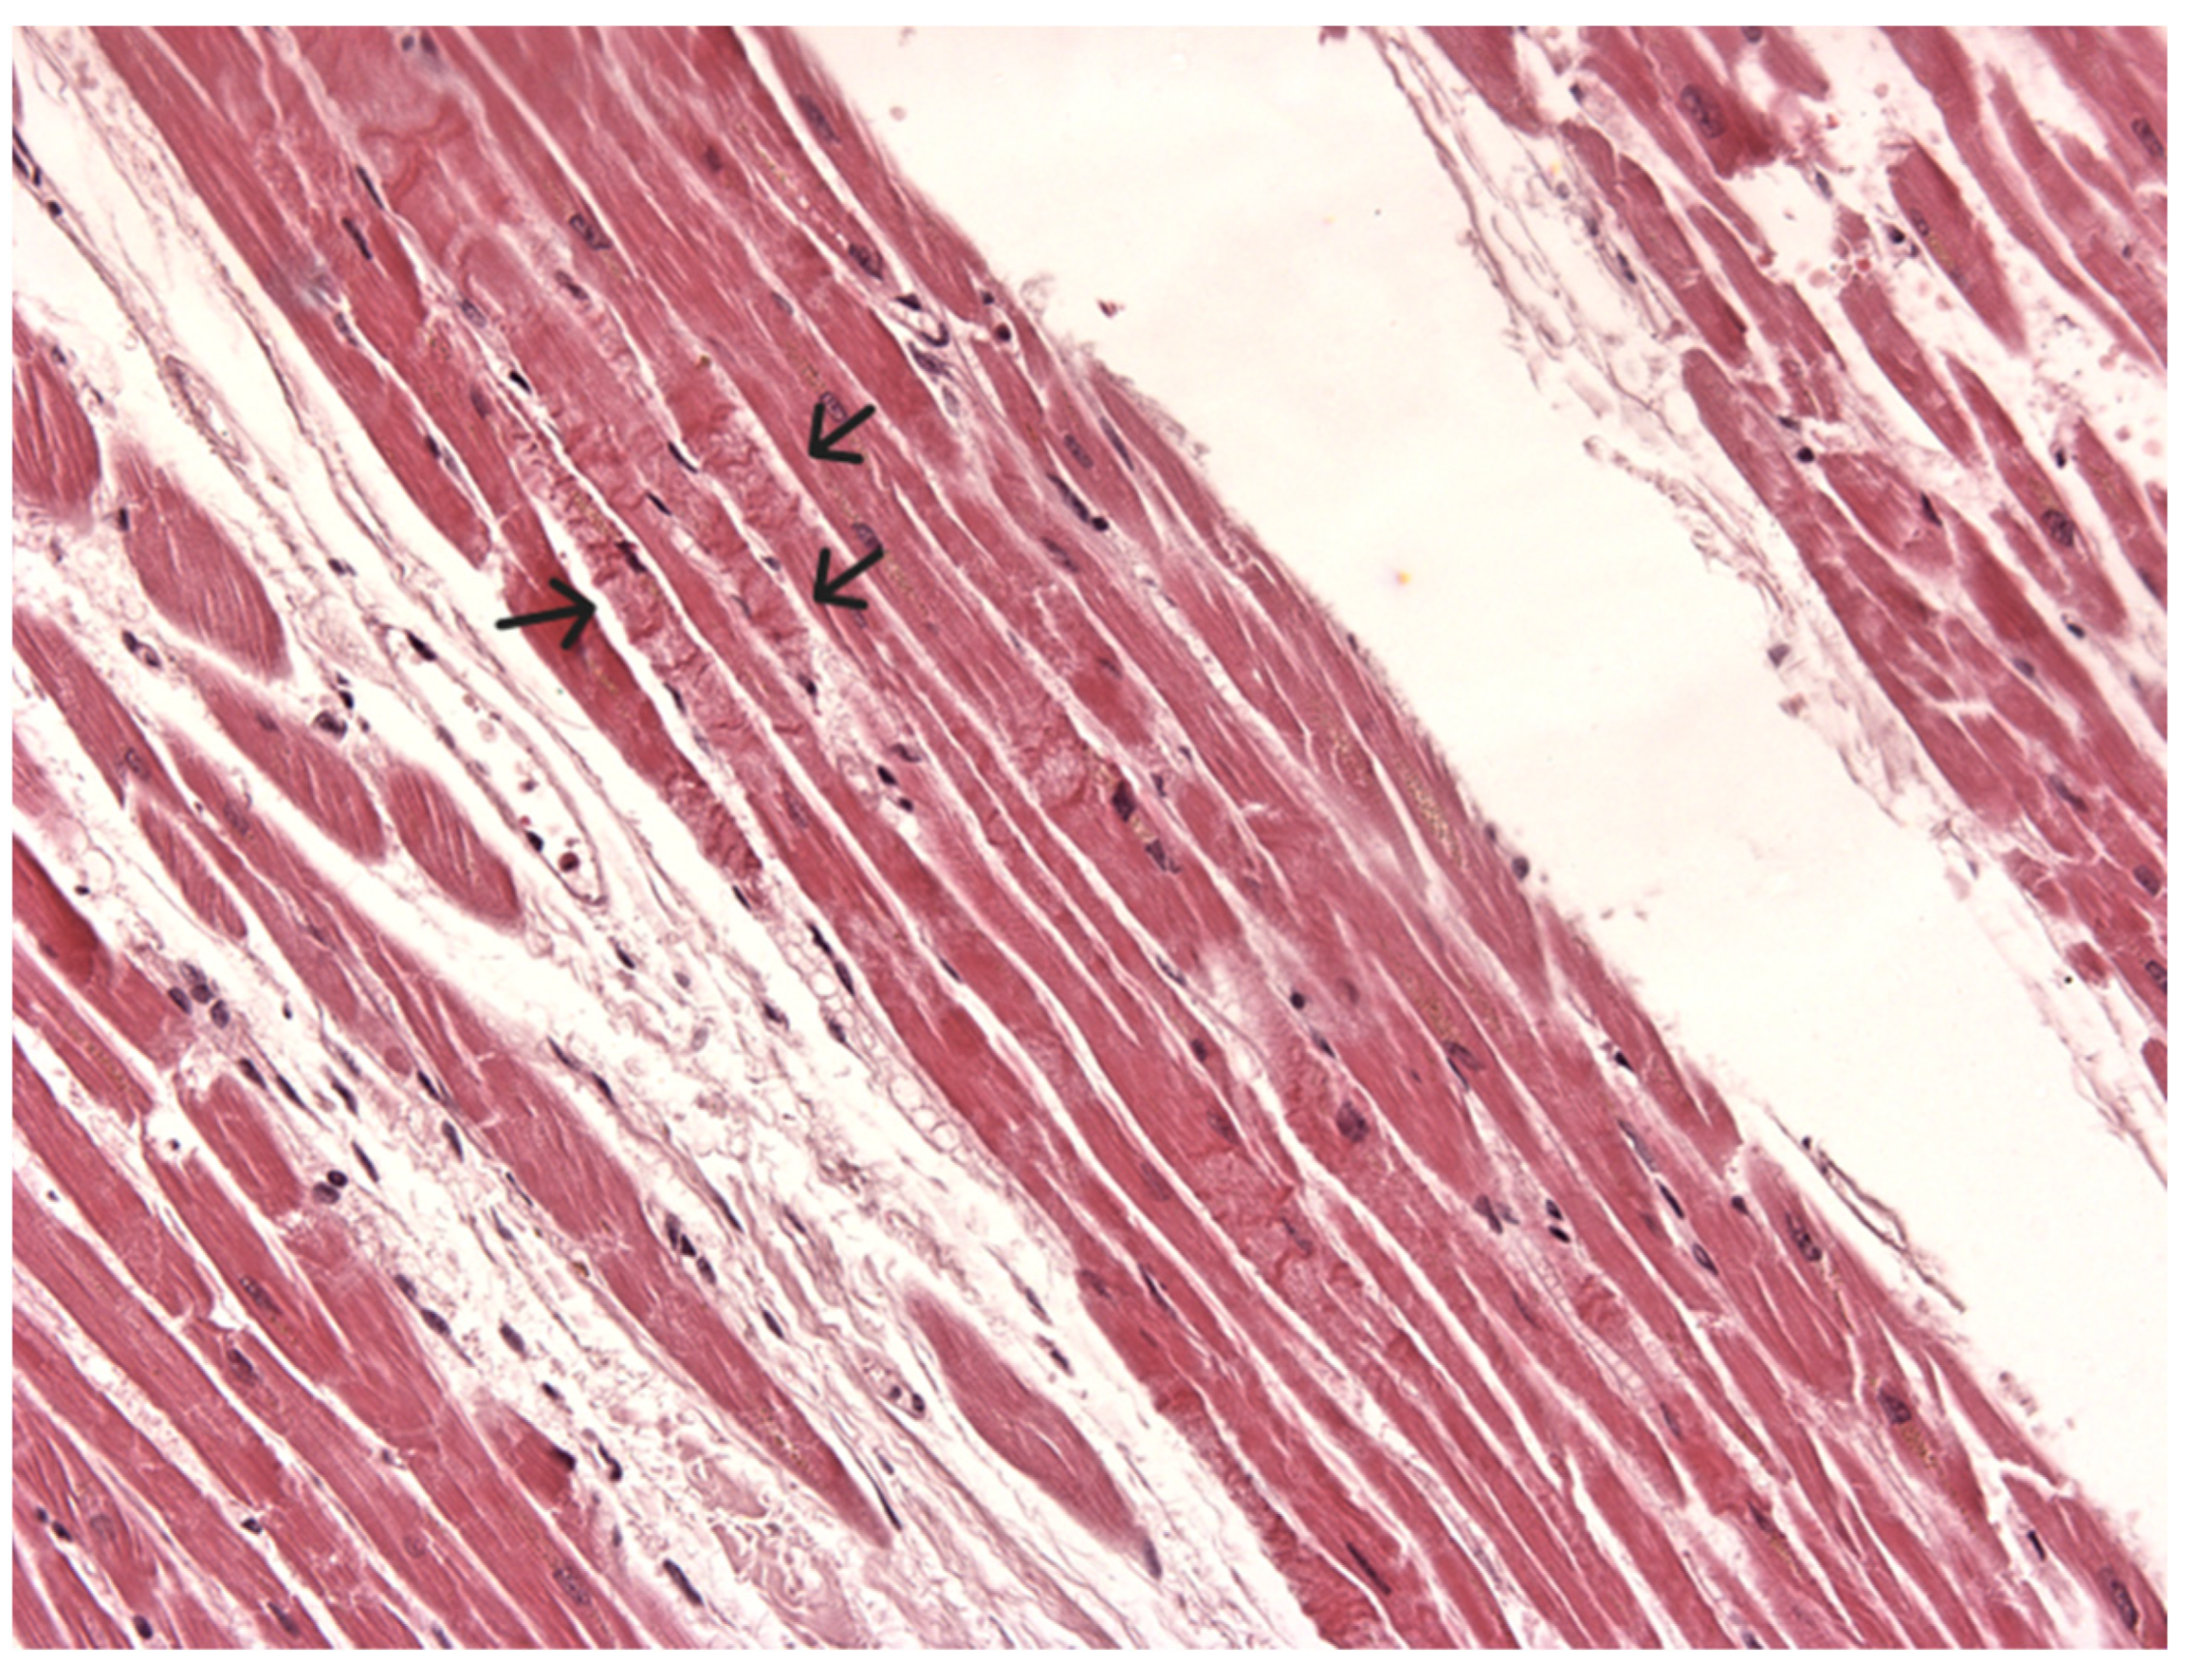

| 10 M | 2 cm in diameter, filling the third ventricle | Severe headache, vomiting attacks | Acute cardiac arrest due to hypothalamus stimulation | Cyst: single stratum of cuboidal, semi-flattened, unciliated, and ciliated epithelial cells lying on a thin collagenous membrane/ Strongly PAS positive Brain: severe edema Heart: hypercontracted myocardial cells, short sarcomeres, very thick Z lines, myofibrils rhexis into cross-fiber | Turillazzi et al. (2012) [17] |